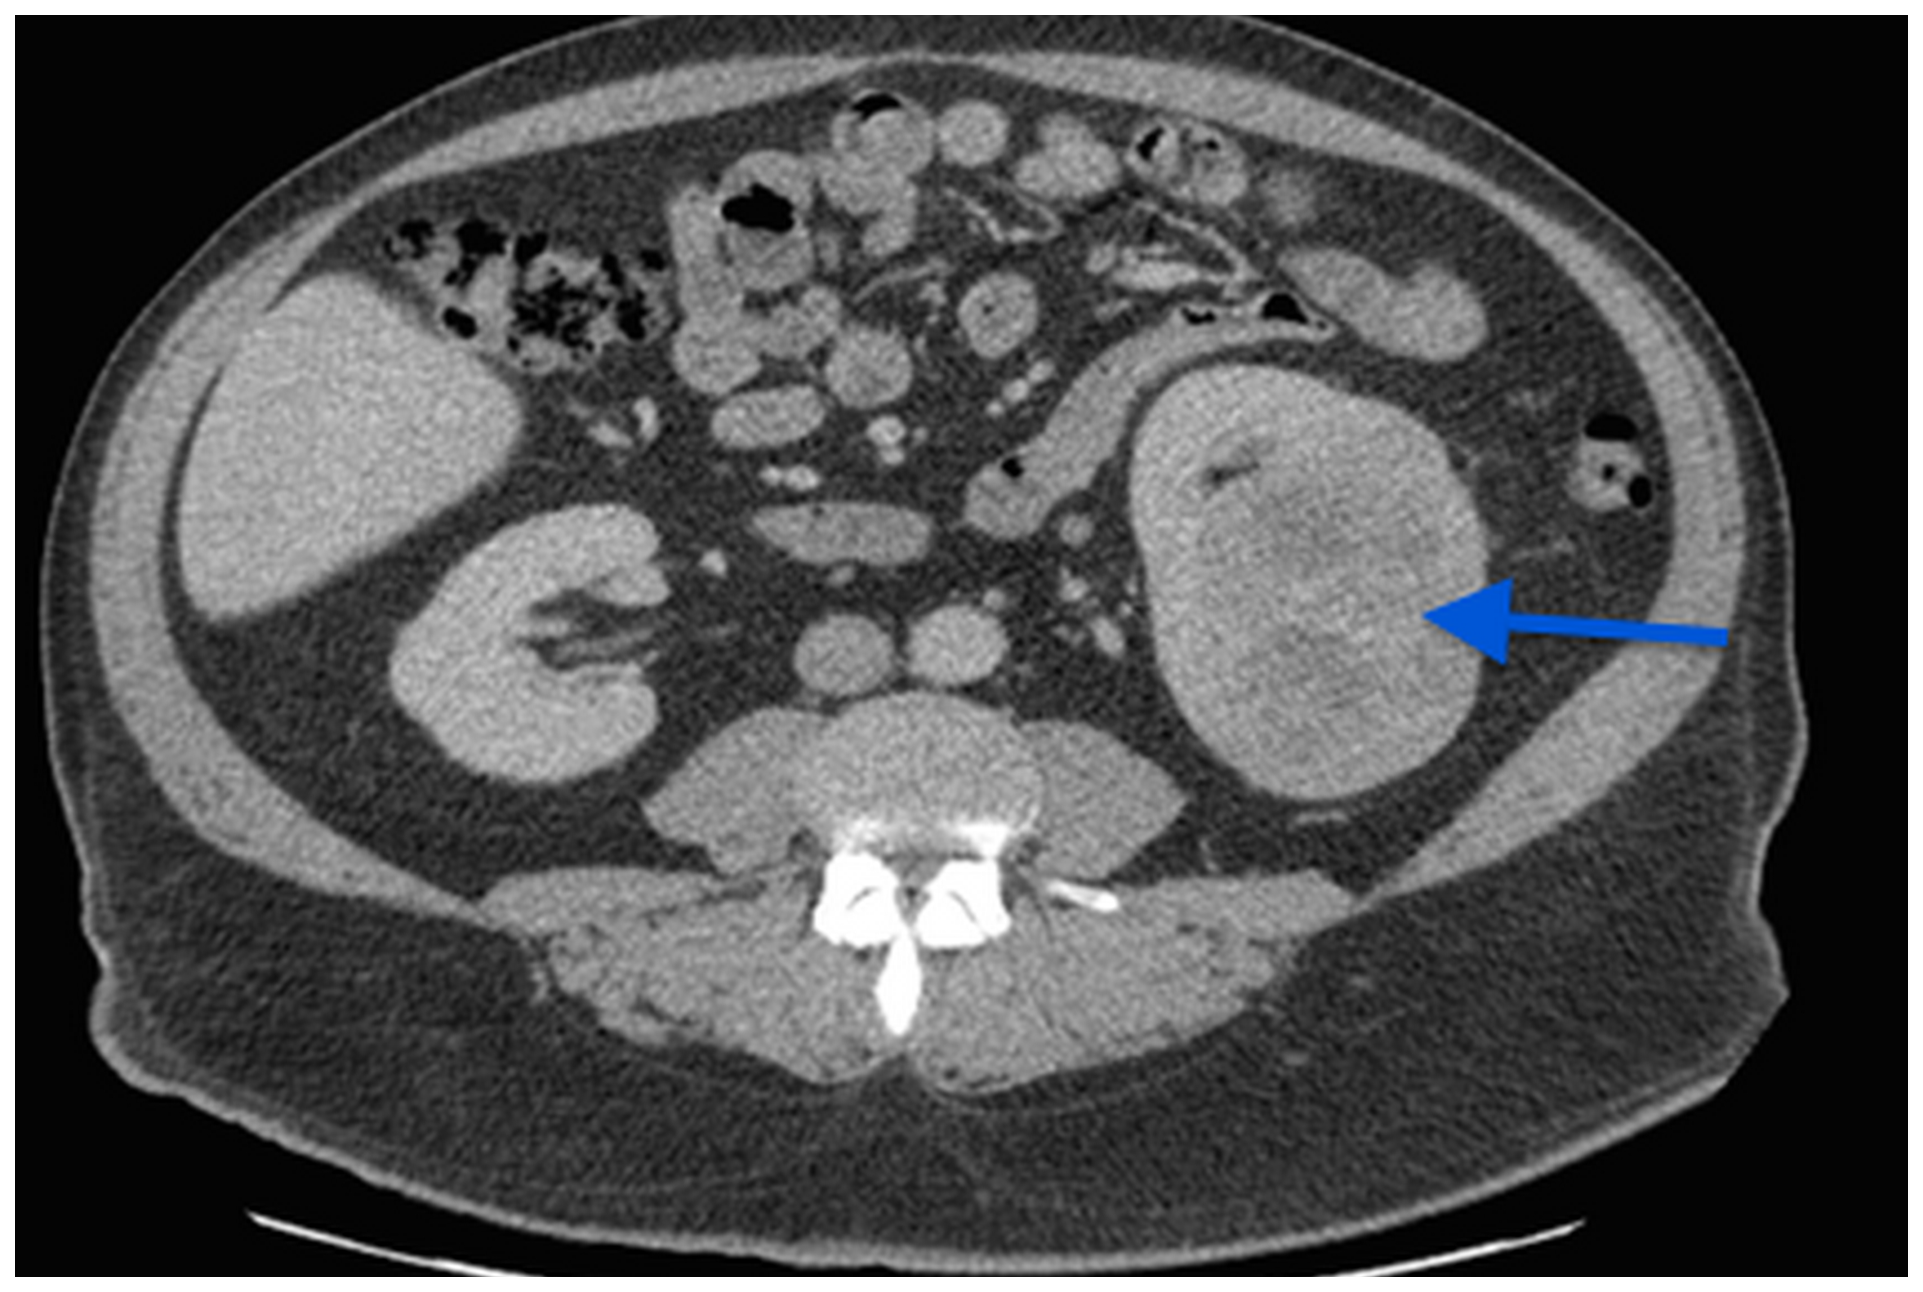

Figure 1: A CT scan image showing a 7 cm left kidney mass.